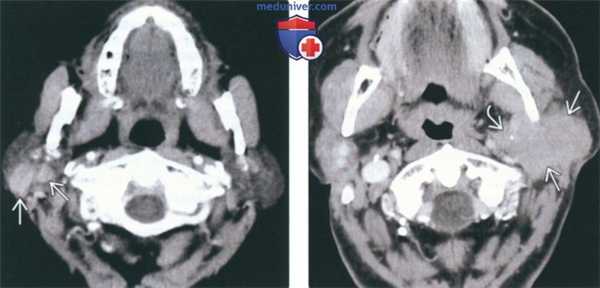

(Слева) КТ с КУ, аксиальная проекция. Множественные образования с четкими контурами, равномерно накапливающие контраст, расположенные в обеих околоушных железах. Околоушные лимфоузлы размерами >1 см заслуживают пристального внимания: возможно, это множественная опухоль Вартина, множественное метастатическое поражение лимфоузлов, либо поражение лимфоузлов при лимфоме. В первую очередь необходимо оценить состояние всех других шейных лимфоузлов.

(Справа) КТ с КУ, аксиальная проекция. Выраженная шейная лимфаденопатия, затрагивающая лимфоузлы I и II уровней. В этом случае у пациента имеется поражение околоушных лимфоузлов при множественной лимфоме. (Слева) МРТ Т2ВИ FS, аксиальная проекция, пациент с припухлостью в области правой щеки: по сравнению с левой околоушной железой правая железа несколько увеличена в размерах, отмечается диффузное усиление сигнала. На выполненной до этого КТ с КУ не было обнаружено ни конкрементов, ни каких-либо других изменений.

(Слева) На аксиальной КТ с КУ визуализируются множественные двухсторонние образования равномерно накапливающие контраст. Узлы в околоушной железе ≥ 1 см требуют дообследования, т.к. могут представлять собой множественные опухоли Уортина, метастатические лимфоузлы или множественное поражение лимфоузлов при лимфоме. В первую очередь необходимо оценить другие отделы шеи на предмет лимфаденопатии.

(Справа) На аксиальной КТ с КУ у этого же пациента определяется распространенная лимфаденопатия верхних отделов шеи, в т.ч. I в и II уровня. В этом случае поражение паротидных лимфоузлов обусловлено системной лимфомой. (Слева) На аксиальной МРТ (Т2 ВИ FS) у пациента с вздутием правой щеки определяется легкое контрастное усиление и диффузный гиперинтенсивный сигнал в правой околоушной железе по сравнению с левой. На КТ с КУ, выполненной ранее, не было обнаружено патологических изменений, в т.ч. конкрементов.